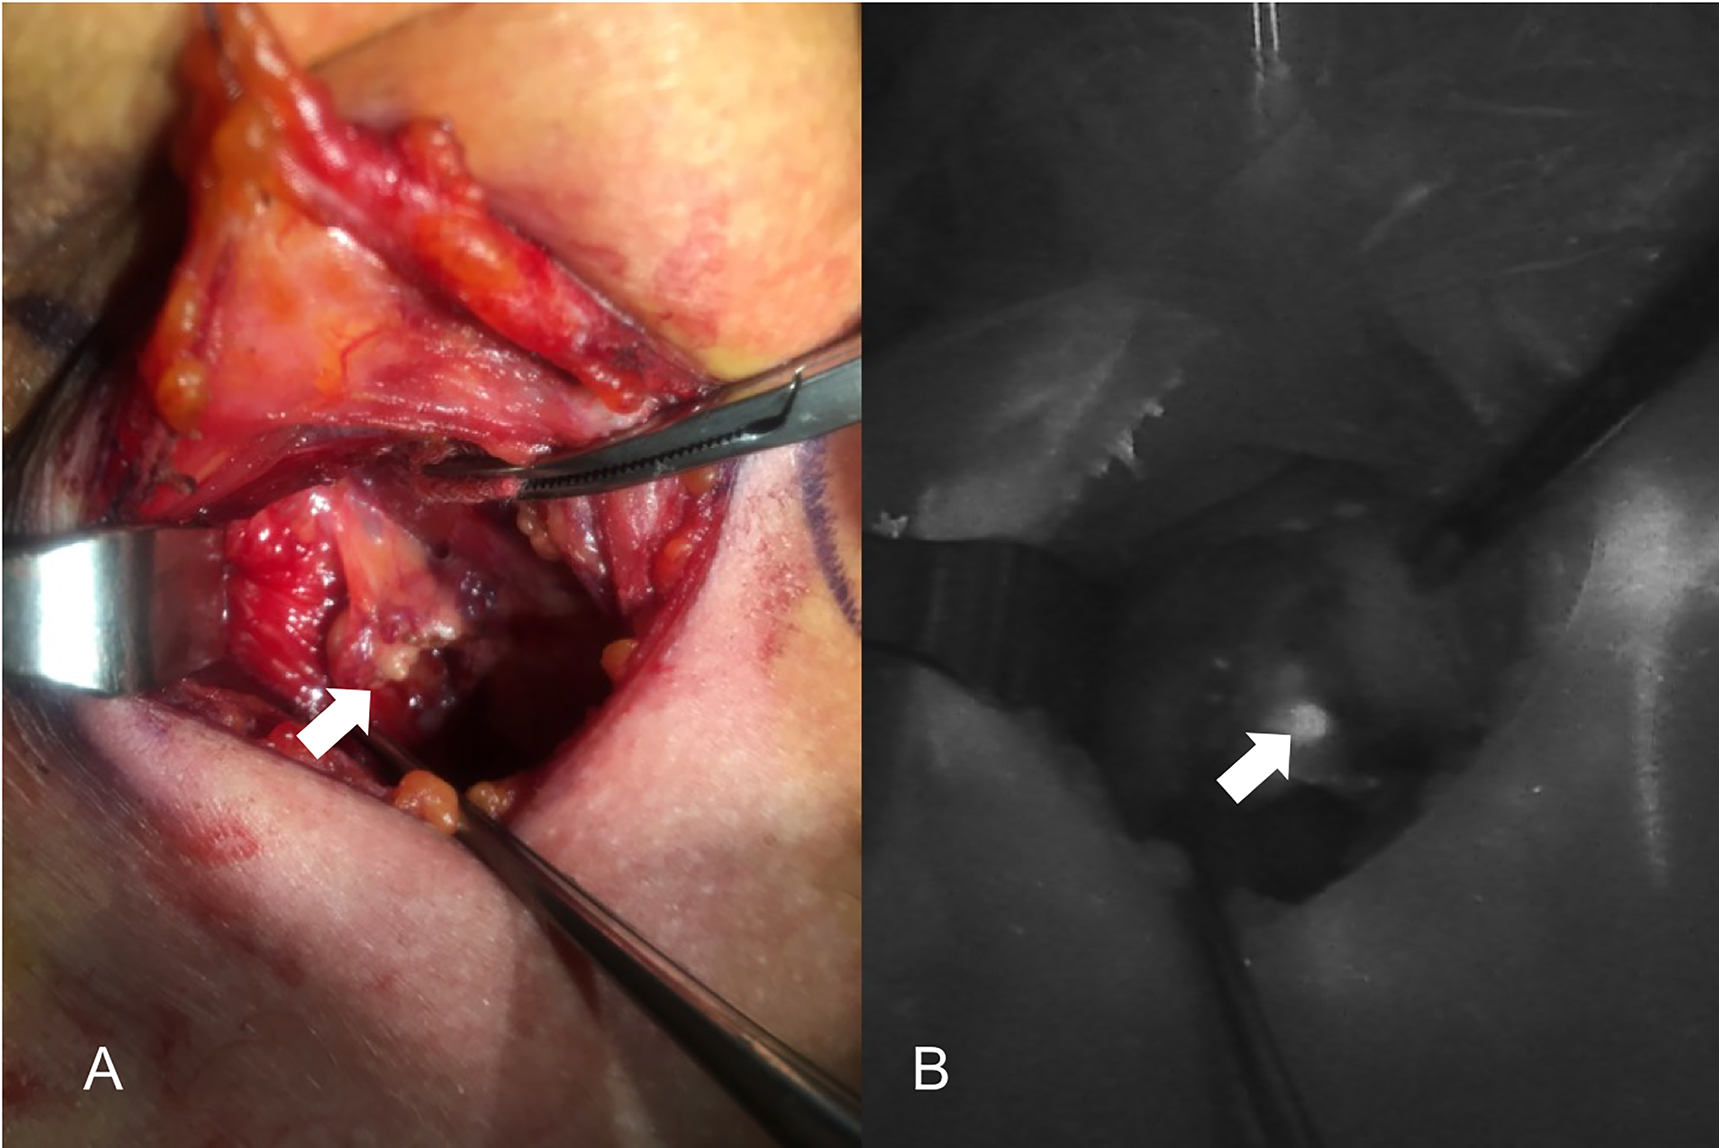

The introduction of NIRAF has vastly improved intraoperative imaging [47, 48]. Many recent studies (Table 2) have demonstrated that the use of NIRAF during thyroid surgery can improve surgical outcomes by facilitating PG identification (Figures 1 –3), which reduces the incidence of postoperative hypoparathyroidism. In particular, Benmilloud et al. showed that NIRAF improved PG identification and helped to reduce the rate of temporary postoperative hypocalcemia, parathyroid autotransplantation, and inadvertent parathyroid resection [48, 66]. In the literature, NIR devices have been shown to facilitate parathyroid gland identification by detecting their AF before conventional, visual recognition by the surgeon, in 37–67% of cases [49]. Additionally, these devices enable the early identification of PGs before surgical dissection, helping to preserve their vasculature [50]. A systematic review and meta-analysis by Barbieri et al. found that NIR fluorescence imaging reduced short and medium-term hypocalcemia compared to conventional surgery [51]. Moreover, NIRAF can detect subcapsular/intrathyroidal PGs or PGs that have been accidentally removed, which can then be resected from the thyroid specimen and auto planted back into the patient (Figures 4 and 5). In addition to the identification of normal PGs, NIRAF can help to identify a pathological PG. Parathyroid adenomas exhibit a more heterogeneous and less intense autofluorescence signature than that of normal PGs (Figure 6), enabling the differentiation between a normally functioning and a pathological PG [52, 53]. Furthermore, the fluorophore is resistant to freezing, heating, and fixing with formalin, meaning that the autofluorescence properties are preserved after gland resection [4, 29, 42, 43].

Three phases of dissection of subcapsular parathyroid (indicated with a white arrow), which was detected using Fluobeam LX near-infrared autofluorescence (NIRAF) imaging. The parathyroid gland (PG) can then be transplanted.